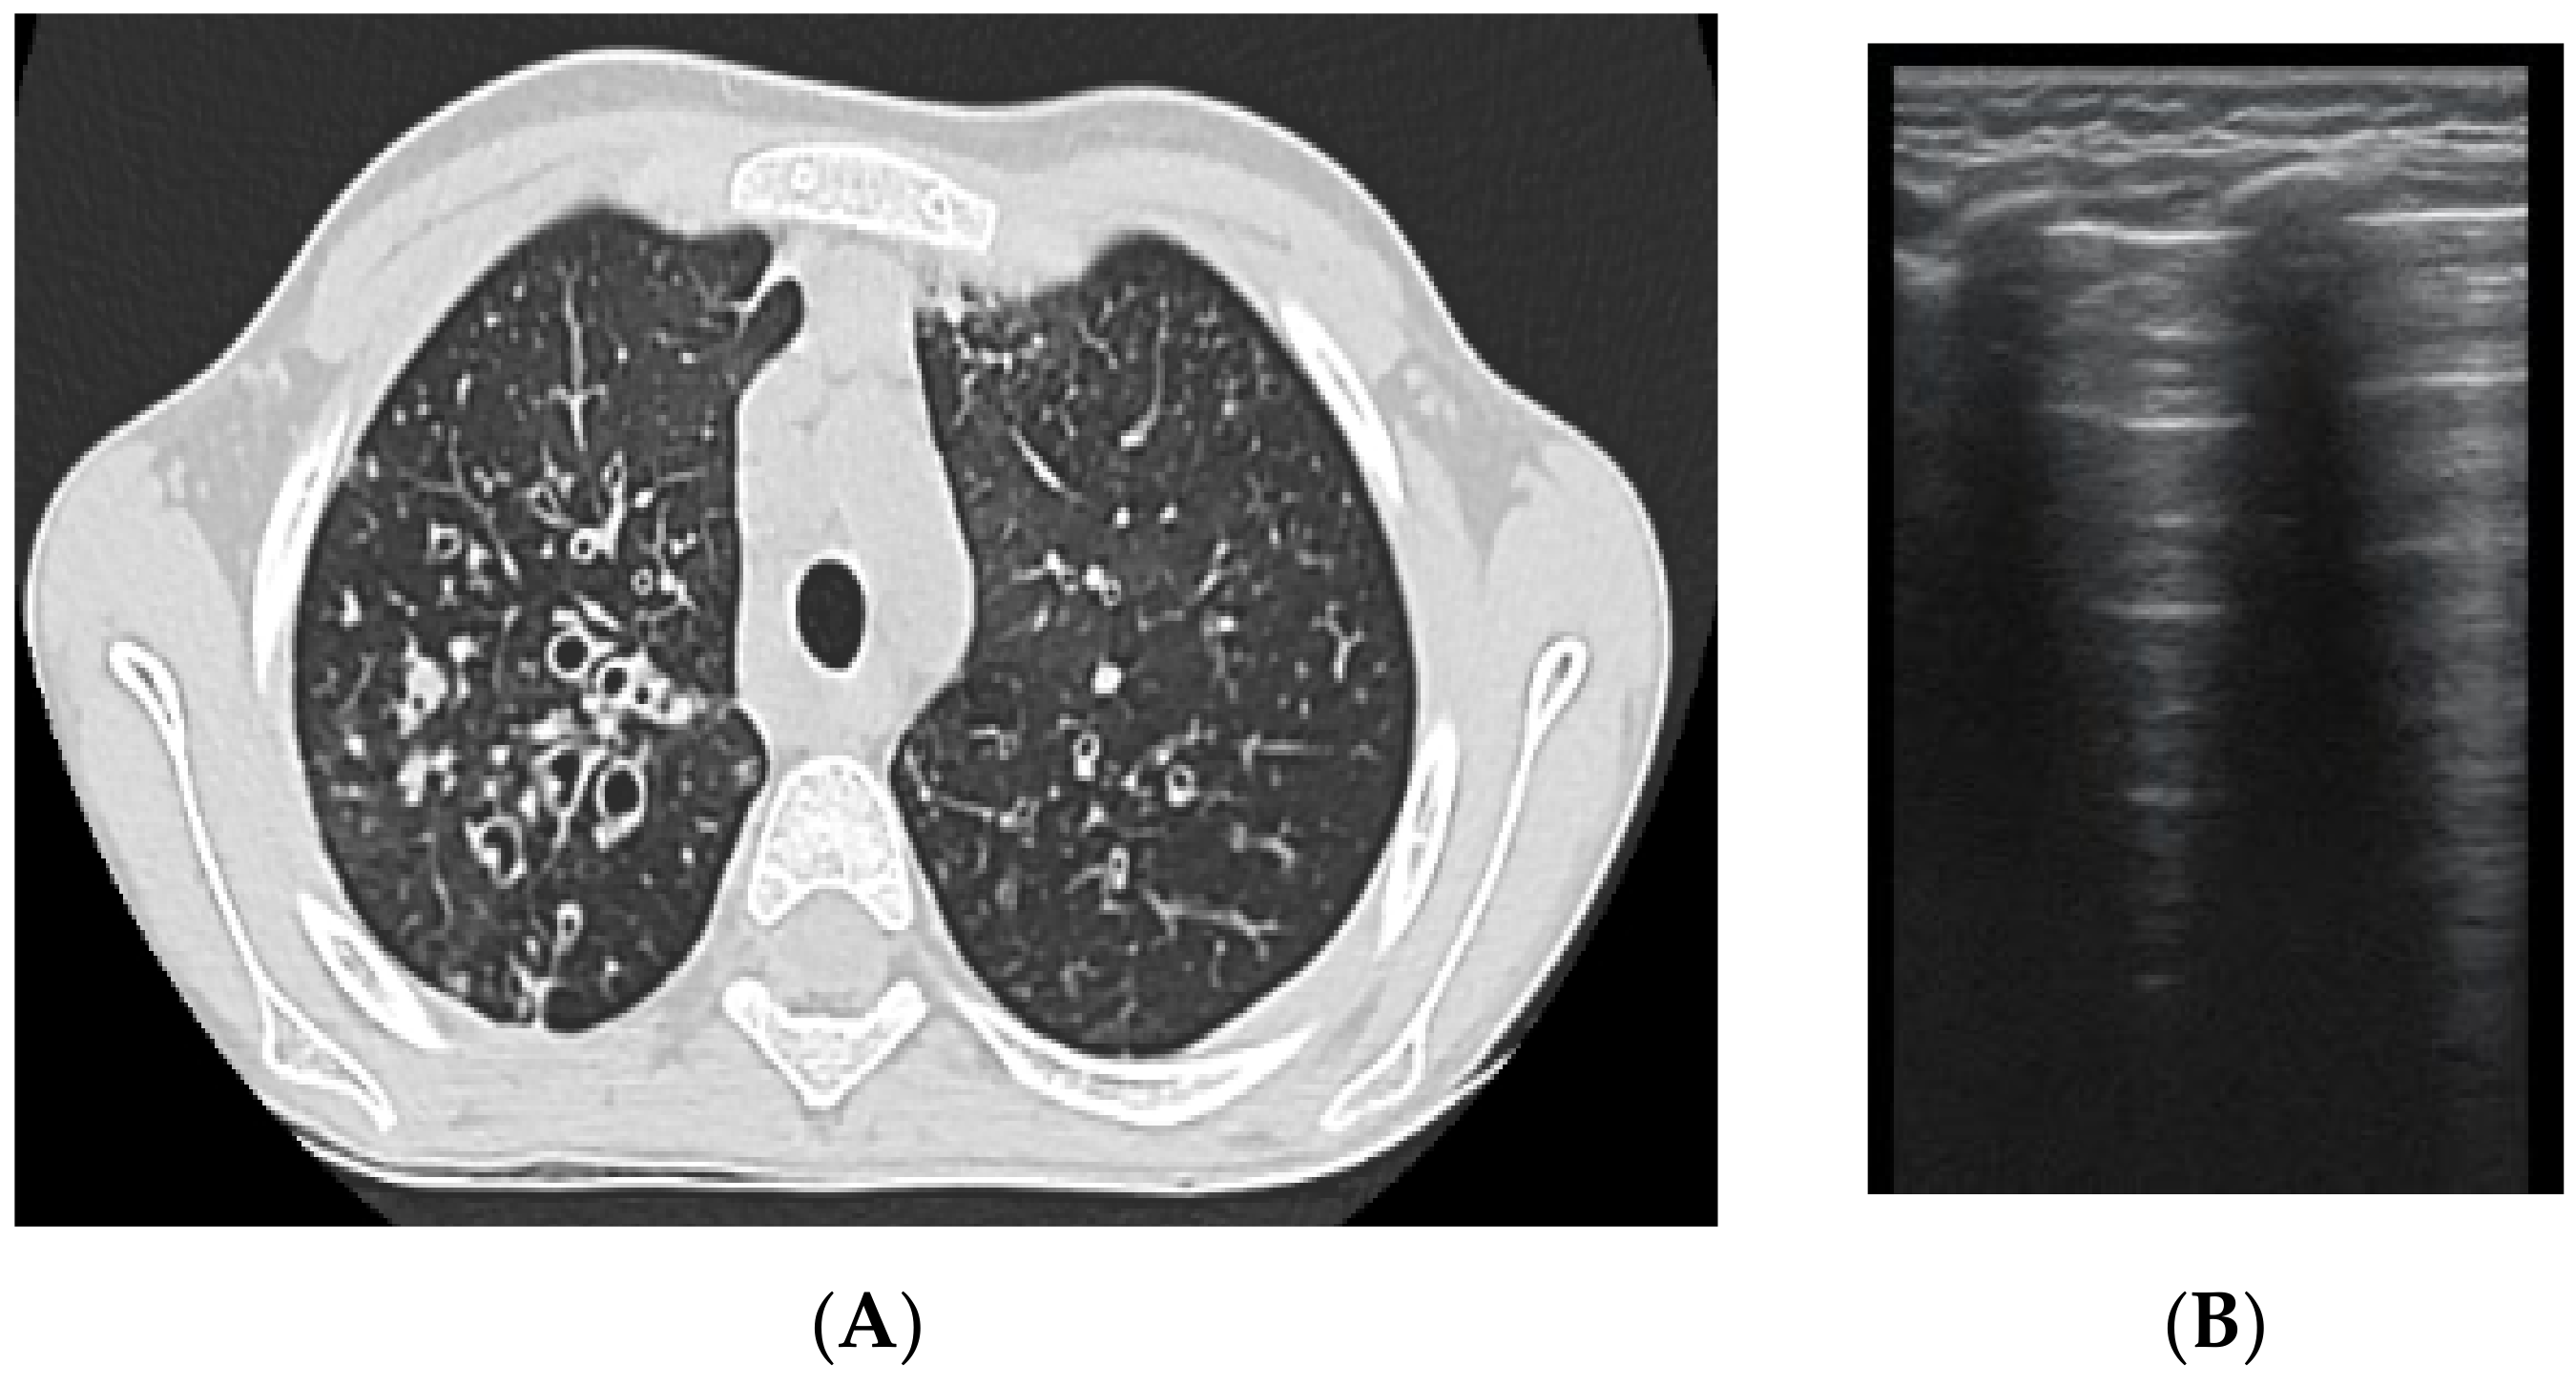

The artefacts used to define the pathological elements were as follows (Table 1): the presence of A lines—normal aspect = 0 points; less than 3 B lines, thin (< 2 mm in width)/intercostal space = 0 points; more than 3 distinctive B lines or 1 coalescent B line = 1 point, quantifying interstitial inflammation or small bronchiectasis (Figure 1) confirmed by CT (Figure 2); more than 2 coalescent B lines = 2 points, suggestive of alveolo-interstitial inflammation or mucus plugging with loss of aeration; either bronchial wall thickening or subpleural consolidation < 1 cm = 3 points, associated with the absence of A lines quantified either as small atelectasis or cystic bronchiectasis with mucus plugging; subpleural lung consolidation > 1 cm, without bronchogram = 4 points; quantified atelectasis (Figure 3)/consolidation with bronchogram = 5 points.

Subpleural consolidation were detected by CT scan (Figure 4) in 33.3% of patients, and confirmed by LUS in 31.5% (Figure 3).

Figure 3. LUS: subpleural consolidation of 1.75 cm/0.78 cm, surface of 0.96 cm2 (score 4), without bronchogram, with adjacent B lines (2 points); A lines also present, examination of left posterior hemithorax.

Figure 4. CT scan of the same patient, with various types of bronchiectasis: (1) cylindrical bronchiectasis with moderate bronchial wall thickening; (2) varicose bronchiectasis; and (3) a round/spiculated consolidation, corresponding to previous LUS consolidation. CT score = 62.